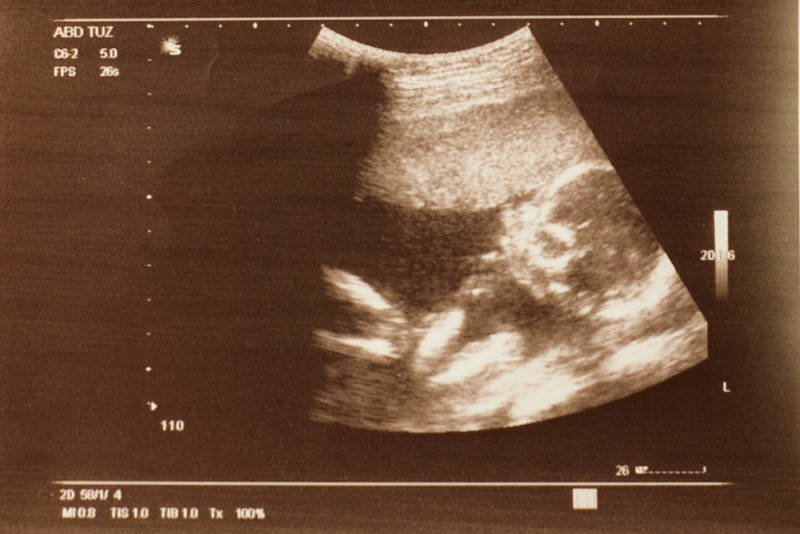

To jest dziecko, które nie ma połowy głowy, ma mózg na wierzchu, ma wiszącą gałkę oczną, ma rozszczep całej twarzy, nie ma mózgu w środku. I będzie umierało dzięki panu profesorowi jeszcze przez najbliższy miesiąc albo dwa. Bo ma zdrowe serce i zdrowe płuca. Będzie umierało, aż w końcu umrze z powodu jakiegoś zakażenia. A kobieta, która urodziła to dziecko - w związku z tym, że ten dzieciak miał głowę większą niż w ciąży donoszonej - musiała mieć zrobione cięcie cesarskie. To jest sukces pana prof. Chazana.